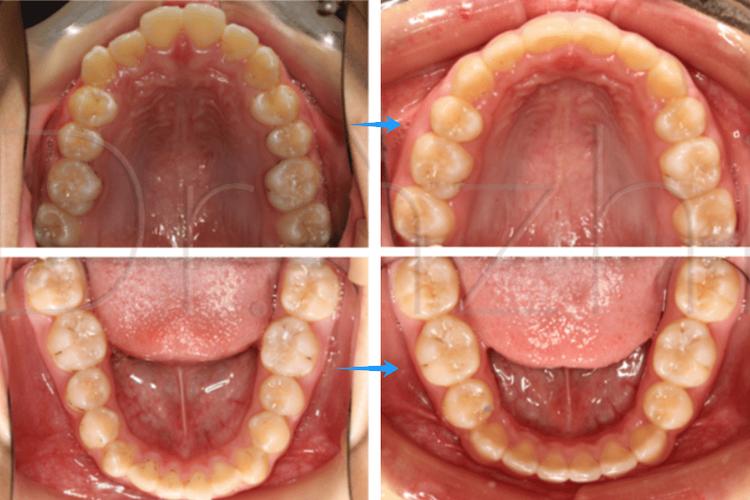

前牙前突(龅牙)

部分孩子因上颌骨发育过度、下颌骨发育不足,或不良习惯(如吮指、咬唇)导致上前牙过度前突,不仅影响美观,还可能导致唇部闭合困难、露龈笑等问题,拔除部分前磨牙后,可以通过“向后移动”前牙,改善牙弓形态,使嘴唇自然闭合,面部轮廓更协调。

(图片来源网络,侵删) -